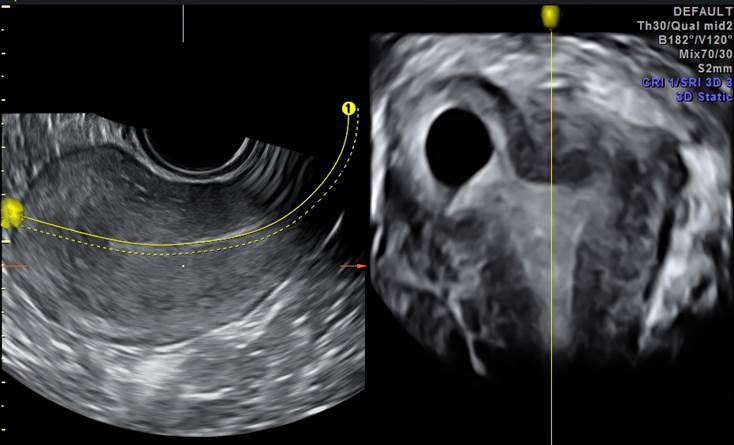

产科_子宫自由解剖切面:节育器与妊娠囊